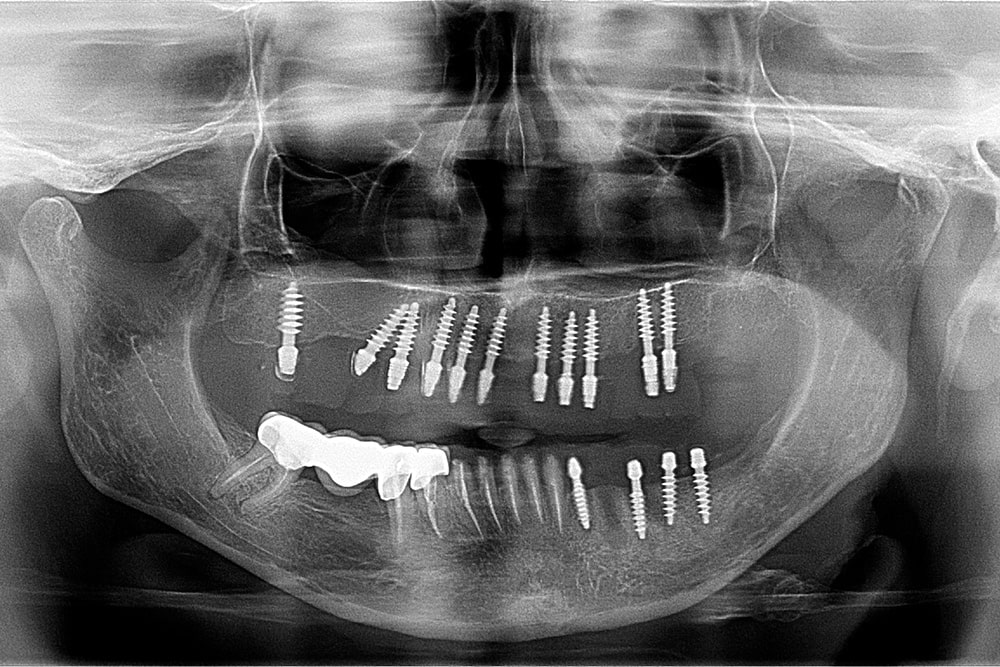

În urma anamnezei și a investigațiilor suplimentare paraclinice (ortopantomogtafie si CBCT), am decis reabilitarea orală complexă cu ajutorul implanturilor și a lucrărilor fixe.

În radiografia de mai jos se poate vedea lucrarea finală efectuată cu succes de către colegii noștri